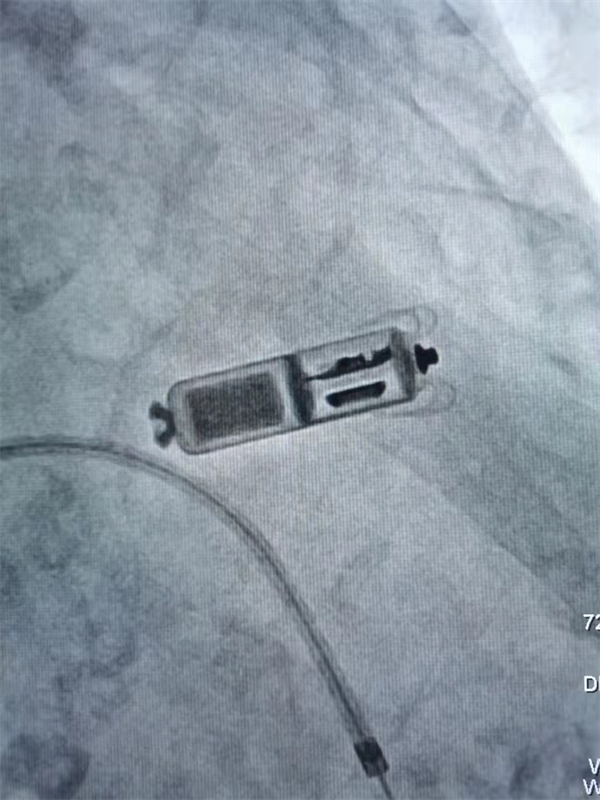

這是目前全世界最小的起搏器,只有1立方厘米大小,就像一顆“膠囊”直接植入心臟,無需切開皮膚做囊袋,也沒有電極導(dǎo)線,手術(shù)創(chuàng)傷更小,還可避免傳統(tǒng)起搏器感染等問題。

而新型“ 膠囊式”起搏器無需植入心內(nèi)膜導(dǎo)線,也無需在胸前皮下制作囊袋放置起搏器脈沖發(fā)生器,這樣就避免了創(chuàng)傷、電極故障、切口感染等風(fēng)險的發(fā)生率。此外,它的體積相比較傳統(tǒng)起搏器減小了93%,僅有膠囊大小,重量約2克。以微創(chuàng)的方式“進(jìn)駐”心臟,無導(dǎo)線,無囊袋,患者甚至感覺不到其存在,成為心臟健康的“隱形衛(wèi)士”。并且擁有超強的電池續(xù)航能力,壽命可達(dá)10年之久,同時兼容1.5T(特斯拉)/3.0T核磁共振掃描的創(chuàng)新功能,可以為心臟提供持續(xù)穩(wěn)定無憂的動能,大大改善了患者的生存質(zhì)量。它適合具有起搏器指征且有感染風(fēng)險、無正常靜脈通路、年齡較大、畏懼手術(shù)希望微創(chuàng)切口、對生活質(zhì)量有較高要求的患者。